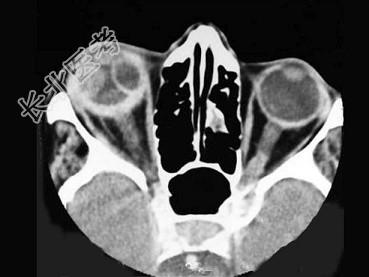

- 多项选择题成人,男, 右眼外伤后视物不清,CT扫描如图所示, 正确的描述或诊断是 ( )

A、右侧玻璃体密度增高

B、右侧眼环增厚,密度增高

C、右侧玻璃体出血

D、右侧视网膜剥离

E、右侧眼球破裂